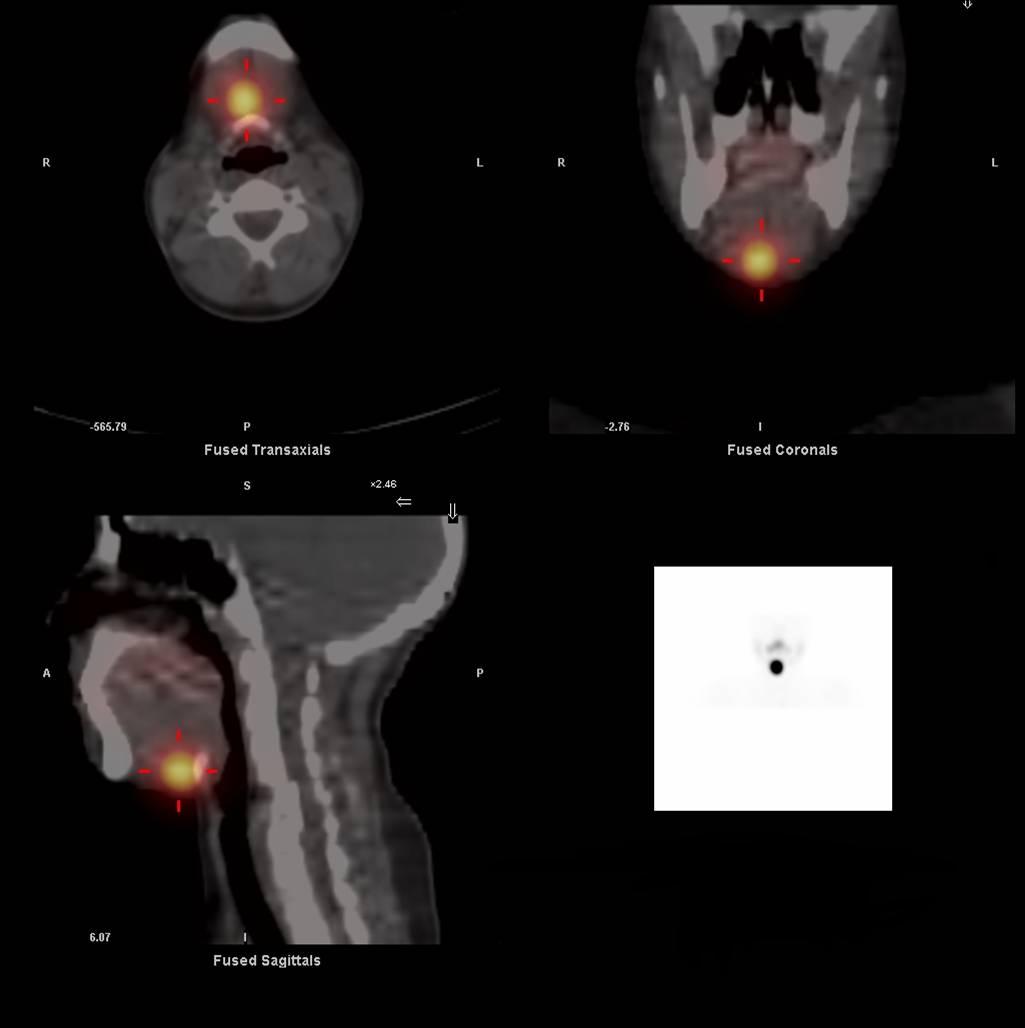

Fixation rapide et intense du technétium dans la région sublinguale

De forme globalement arrondie

Correspondant à la masse visible à l’échographie (nodule hypervascularisé en positon sous linguale de 25 x 22 x 15mm) et compatible avec du tissu thyroïdien.

Nodule chaud au sein du tissu thyroïdien ectopique.